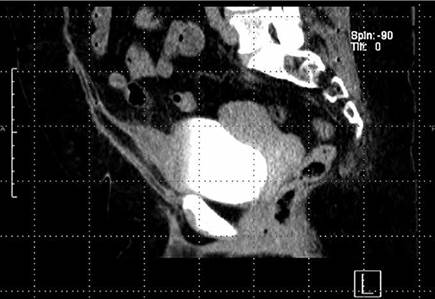

FIGURA 3: TAC sagital fase de eliminación tardía: mayor llenado de la vejiga por el medio de contraste al mismo tiempo mayor llevado del divertículo uracal, mismo que se muestra comoprotrusiónfocal del domo vesical, con engrosamiento de sus paredes mucosas y estriación de la grasa adyacente

FIGURA 3: